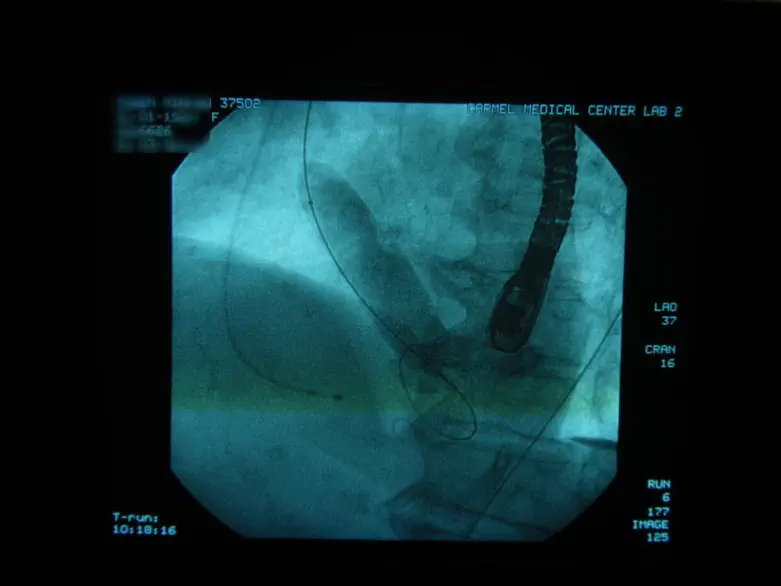

בשיטה החדשה הנקראת TAVI מוחדר המסתם החדשני באמצעות צנתר ישירות אל הלב, הרופא המצנתר פותח את המסתם בצורת מטריה בתוך לב החולה, ומבצע החלפה מלאה של המסתם הפגוע במסתם החדש, וכל זאת מבלי לחתוך שום דבר בגוף ומבלי לגעת בלב כלל.

"היתרונות של השיטה החדשה הם עצומים ומהווים בשורה ענקית לחולי הלב", מסביר פרופ' דוד הלון, מנהל יחידת הצינתורים בבית החולים כרמל, "אנחנו חוסכים מהחולה ניתוח לב פתוח, שזה פחות פתיחת החזה, פחות כאבים, פחות תרופות, פחות הרדמה, ההחלמה מהירה והחזרה לשגרה הינה בזמן קצר ביותר".

את הצינתור הראשון בבית החולים כרמל ביצע צוות משולב של מצנתרים וקרדיולוגים בכירים בשיתוף מחלקת הרדמה ומנתחים מהמחלקה לכירוגיית לב וחזה בבית החולים. פרופ' ראובן פיזוב, ד"ר רונן יפה, ד"ר נאדר חדר ,ד"ר אמנון זלוטניק , ופרופ' לברוד זא'ן קלוד, מומחה עולמי לצינתורי מסתם, שהגיע במיוחד מצרפת לכרמל לצורך הצנתור.